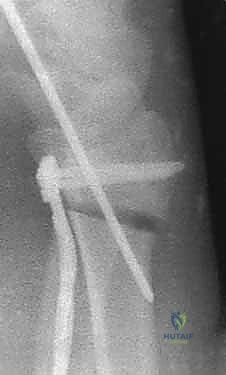

3. قص العظم التصحيحي (The Osteotomy)

بناءً على التخطيط الثلاثي الأبعاد المسبق، يستخدم الدكتور هطيف مناشير عظمية دقيقة جداً لعمل شق في العظم في نقطة التشوه الأصلية. يتم فتح العظم وتعديل زاويته واستعادة طوله الطبيعي.

4. الترقيع العظمي (Bone Grafting)

عندما يتم تعديل زاوية العظم وفتحه، يتكون فراغ عظمي. لضمان التئام سريع وقوي، يقوم الدكتور هطيف بملء هذا الفراغ بطعم عظمي (Bone Graft). يمكن أخذ هذا الطعم من عظم الحوض الخاص بالمريض، أو استخدام بدائل العظم الصناعية عالية الجودة.

5. التثبيت بصفائح التيتانيوم (Internal Fixation)

للحفاظ على الوضع الجديد والمثالي للعظم، يتم استخدام صفائح تيتانيوم متقدمة ذاتية الغلق (Volar Locking Plates). هذه الصفائح مصممة تشريحياً لتلائم شكل الكعبرة، وتوفر تثبيتاً قوياً جداً يسمح للمريض ببدء تحريك أصابعه في اليوم التالي للعملية.